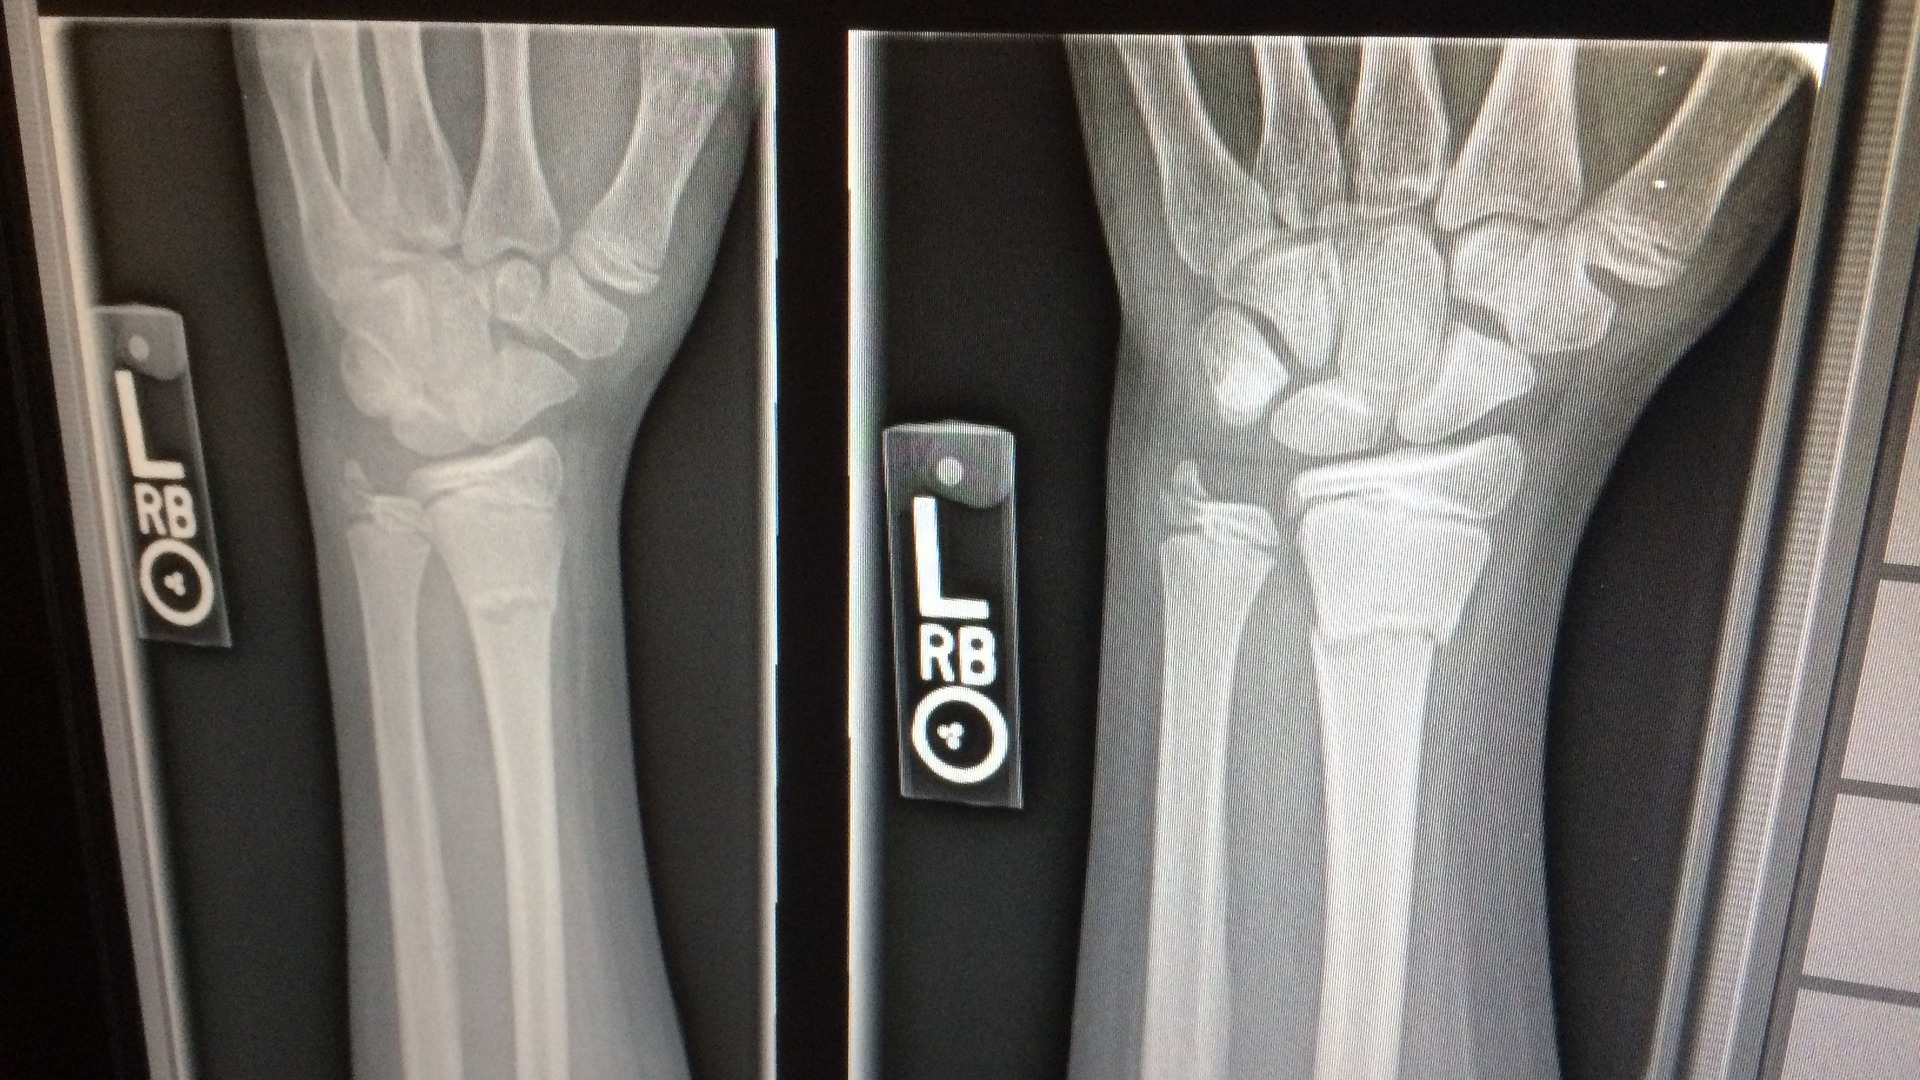

Pri páde z rebríka si niekto poraní ruku tak, že s ňou nemôže ani pohnúť od bolesti. Čo urobíš?

Bez ohľadu na to, čo radili staré príručky, v súčasnosti sa neodporúča robiť so zlomeninou nič. Ak zranený nemôže s končatinou hýbať, ide o jasnú zlomeninu. Len zabezpeč, aby sa vôbec nehýbal, môžeš mu priniesť vodu aby neumrel od smädu, ale ideálne je iba zavolať pomoc a počkať.